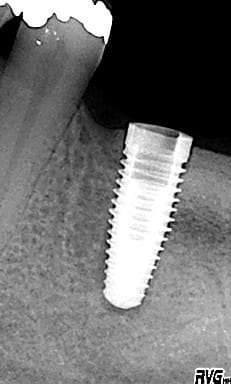

Lors du passage du dernier forêt, la patiente a refermé la bouche lors d'un spasme alors que le forêt était en rotation. Résultat, outre la surprise pour tout le monde, : un surforage apical et mésial dans la dernière moitié.

L'implant était totalement immobile après sa pose.

A priori cela ne m'inquiète pas trop mais j'aimerais avoir l'avis de ceux qui ont rencontré une situation identique.

Replace Tapered WP pour être précis... ;)

Effectivement, c'était ma question. Je pensais connaître la réponse vue l'excellente stabilité primaire mais les avis des autres sont toujours bons à prendre.